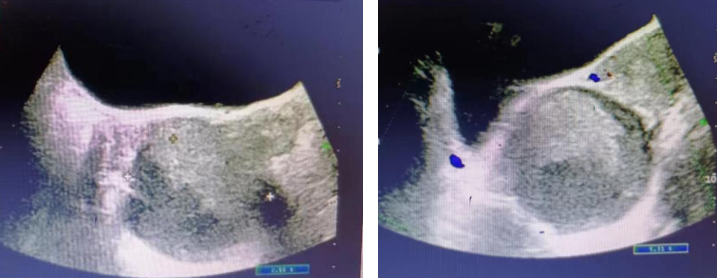

复查超声(2022-06-22):子宫大小约4.2 cm*4.3 cm*3.0 cm,形态未见异常,内膜厚约0.7 cm;右侧附件区见大小约6.5 cm*5.5 cm*5.1 cm囊性回声,边界清,透声差,内见细密点状回声充填,后方回声增强;左侧卵巢未见明显异常。肿瘤标志物:HE4:37.8 pmol/l;CA125:40.9 U/ml(↑);CA199:18.6 U/ml。复发治疗:给予GnRH-a戈舍瑞林3.6 mg皮下注射(2022-06-22~2022-10-15,共5次);之后口服地诺孕素,但因异常子宫出血服用2个月后停药。

复查超声(2022-10-04):子宫大小约3.8 cm*3.7 cm*2.2 cm,内膜厚约0.4 cm;右侧附件区见大小约6.1 cm*4.8 cm*5.5 cm低回声,边界清,形态规整,回声不均;左侧附件区未见明显异常。复查超声(2022-12-19):子宫大小约4.5 cm*3.7 cm*3.2 cm,内膜厚约0.6 cm;右侧附件区见大小约7.2 cm*6.2 cm*6.0 cm混合性回声,边界清,形态规整,内回声欠均,后方回声增强,囊性回声内透声差,充满细密点状回声。复查超声(2023-01-02):子宫大小约4.74 cm*3.2 cm*3.1 cm,子宫内膜厚约0.4 cm;右侧附件区见大小约8.1 cm*6.6 cm*5.3 cm囊性回声,边界清,形态不规整,囊壁较厚,内透声差,其内可见斑片状强回声及细密点状回声。